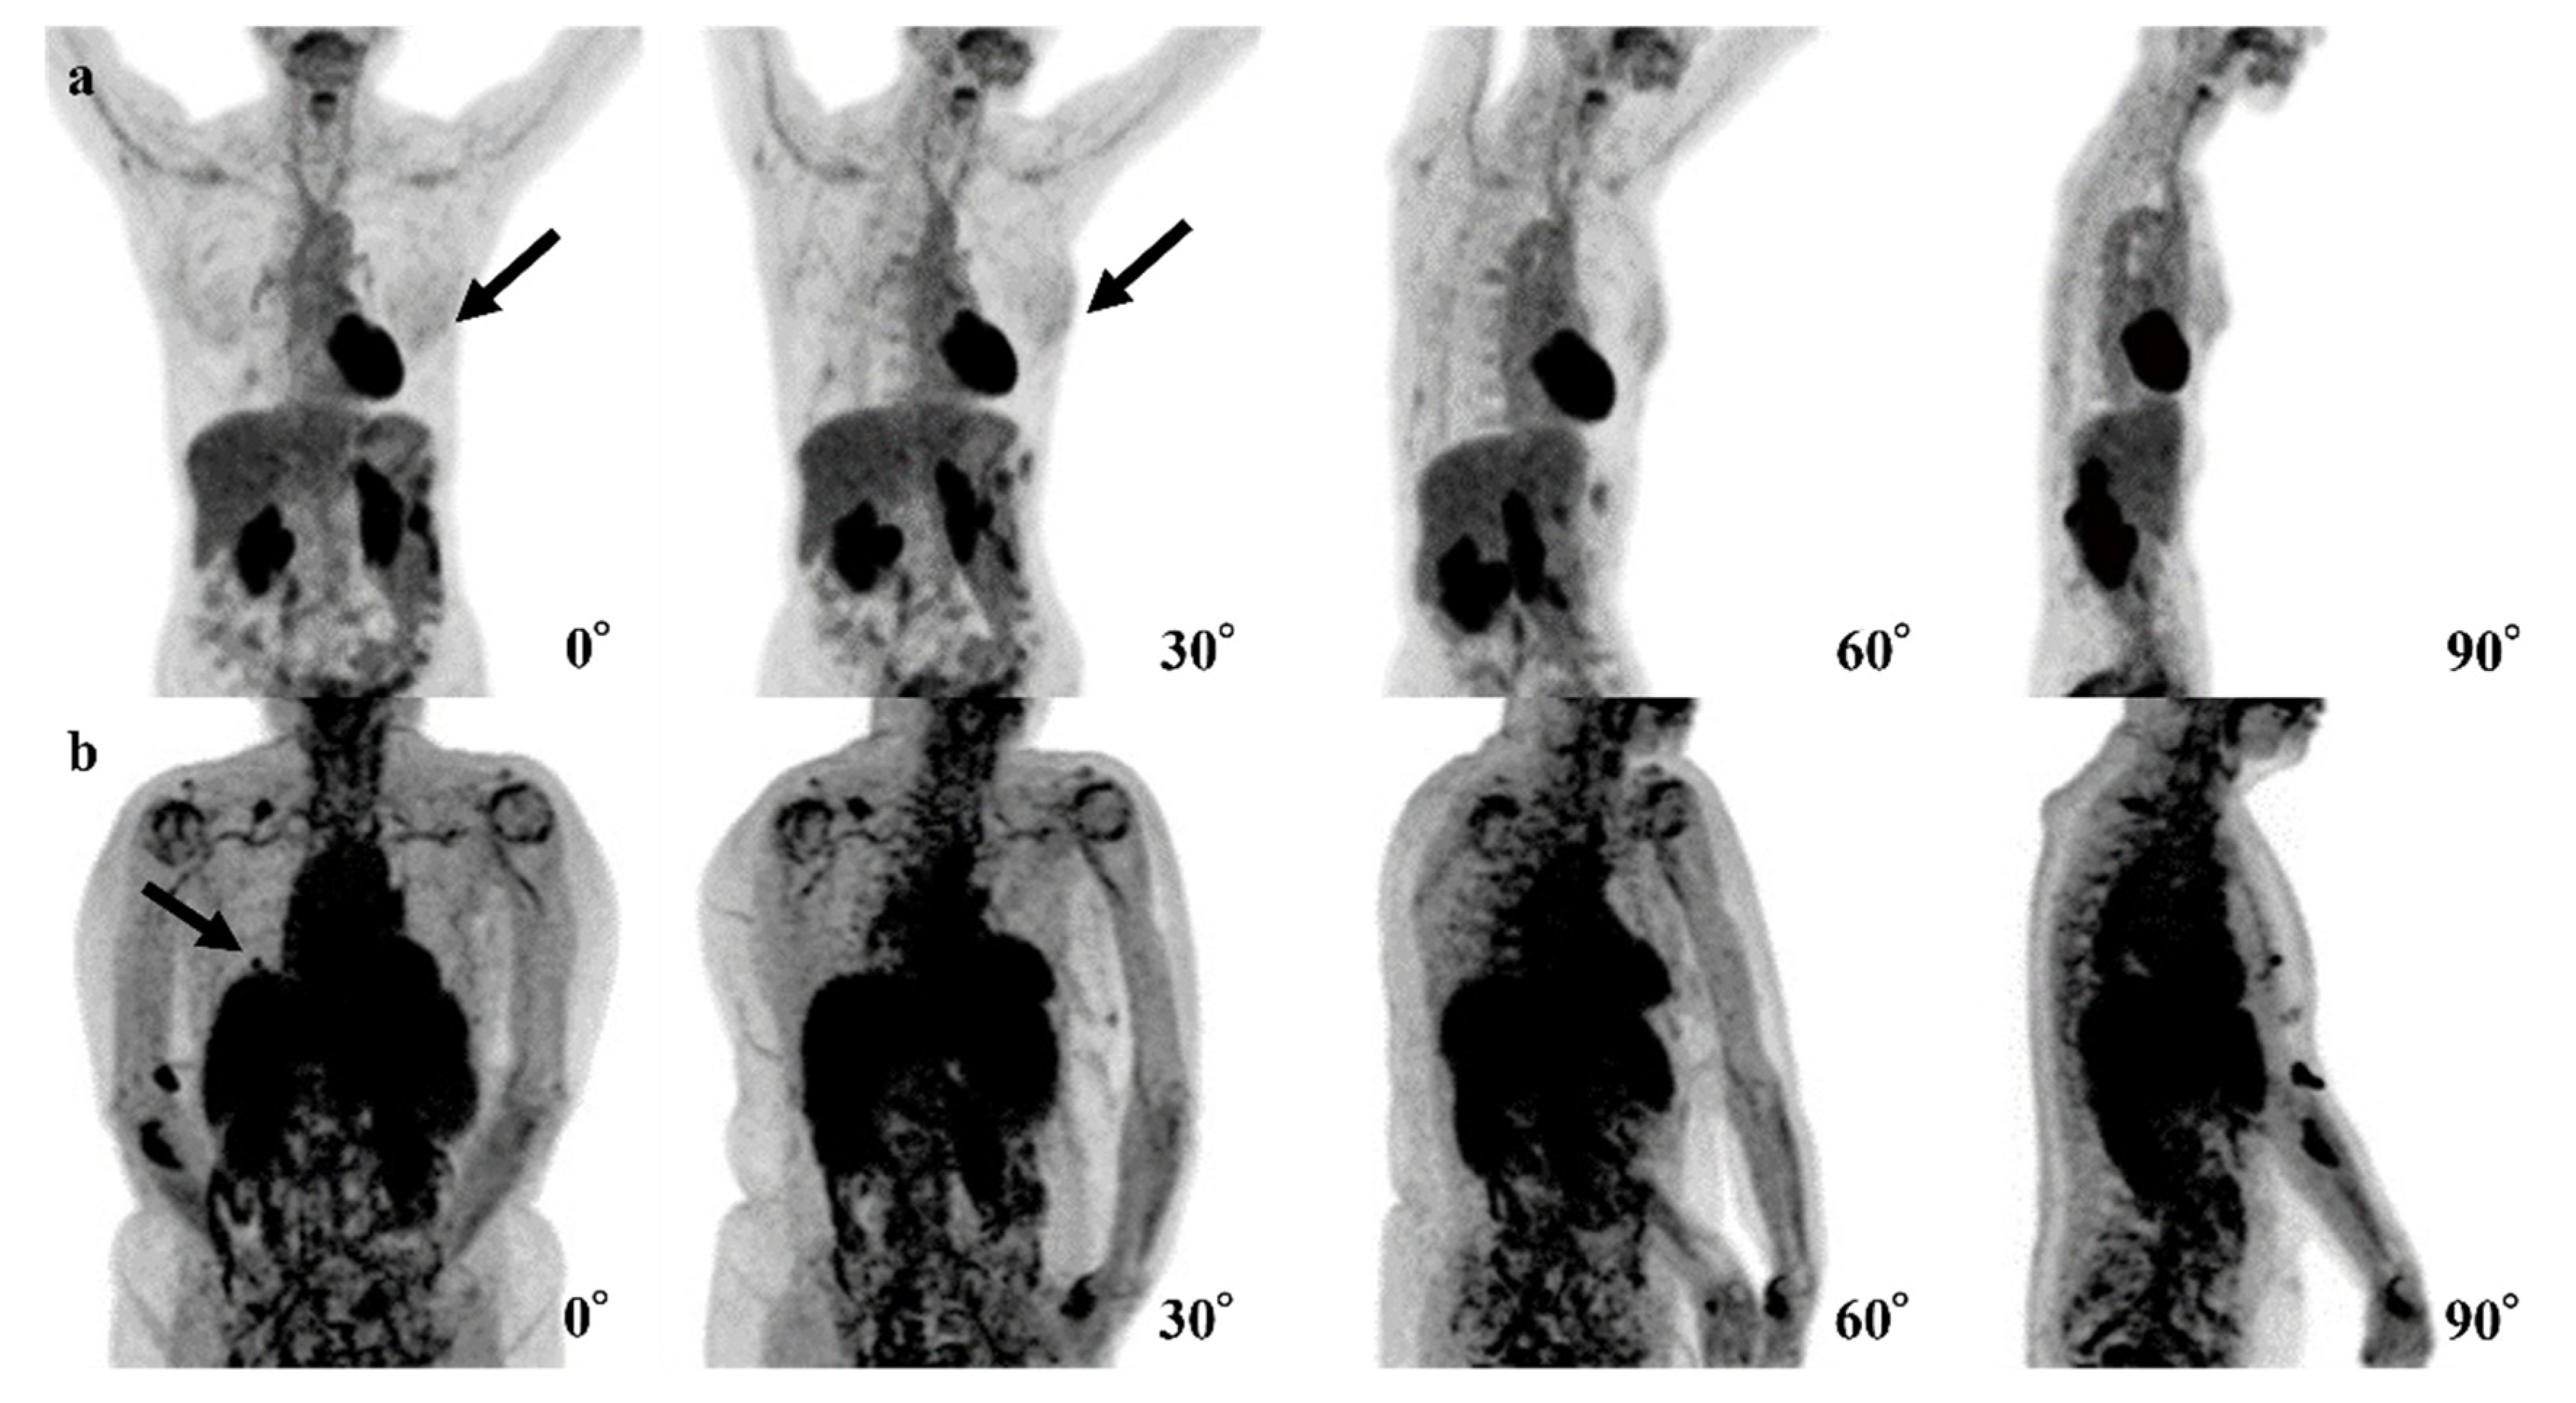

Figure 4.

Examples of false-negative cases of the 4-degree model are shown. (a) The fluorodeoxyglucose (FDG) uptake at left breast cancer (black arrows) is very low and difficult to recognize. (b) The right breast cancer is recognizable in the 0° and 90° positron emission tomography (PET) maximum-intensity projection (MIP) images (black arrows) but is difficult to recognize in the 30° and 60° PET MIP images due to physiological FDG uptake of other organs.

In six cases, the 0-degree model made mistakes, for which the 4-degree model made the correct diagnosis. The FDG uptake of BCs was shown near the nipple in three of these cases, and the shape of FDG uptake in BC was a non-mass-like lesion in another case (Figure 5).

Figure 5.

Examples of the mistakes made by the 0-degree model, for which the 4-degree model are shown. (a) The fluorodeoxyglucose (FDG) uptake at left breast cancer (black arrows) is very low and difficult to recognize. (b) The right breast cancer is recognizable in the 0° and 90° maxi-mum-intensity projections (MIPs) (black arrows) but is difficult to recognize in the 30° and 60° MIPs due to physiological FDG uptake of other organs.

For the three false-negative cases, it is possible that the level of FDG uptake at the lesions was insufficiently high (Figure 5a) or that the high level of physiologic FDG uptake in other organs led the model to avoid recognizing the lesions (Figure 5b). For these reasons, the model seemed not to be able to detect the abnormal FDG uptake. In two of these false-negative cases, the cancer subtypes were ductal carcinoma in situ (DCIS). The size of these lesions might be too small and low FDG uptake to recognize lesions. The remaining case was a small 8 mm invasive carcinoma with low activity and was a luminal A type.